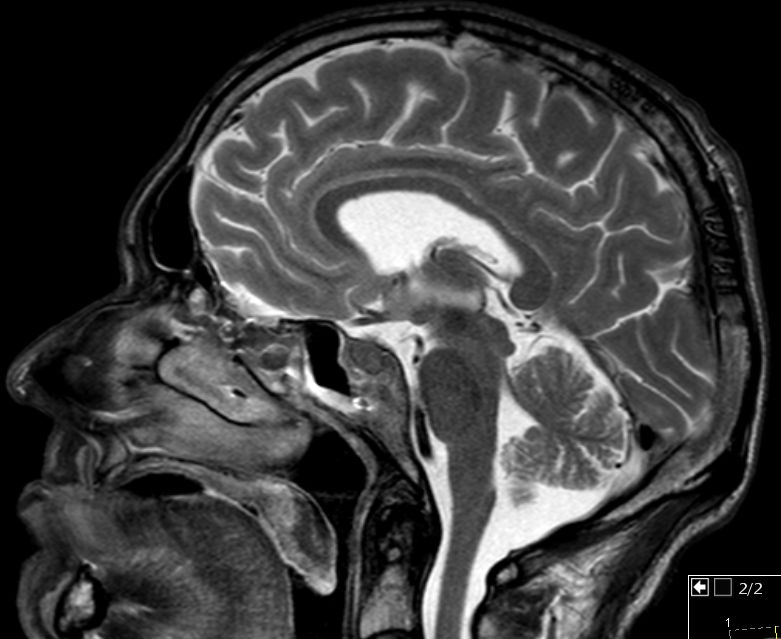

55-jähriger Mann, der vor 6 Monaten wegen eines Oropharynxkarzinoms links pT3 pN0 M0, L1, V0, Pn1 radikal operiert wurde und eine postoperative Radiochemotherapie mit Cisplatin erhielt. Jetzt Schädelbasis-Metastase im Bereich des Sinus cavernosus. Klinisch Hirnnervenausfälle links N. abducens, rechts N. opticus, - trochlearis, - trigeminus 1. Ast, unsicheres Gangbild, Störung des Schluckaktes. | ||